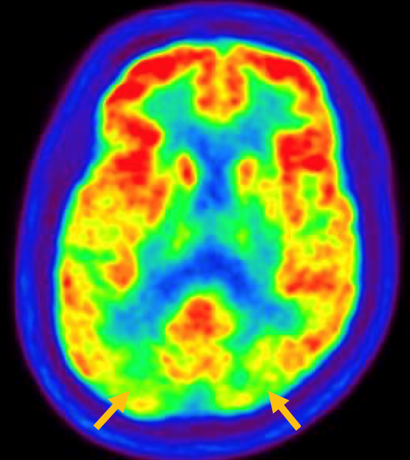

루이소체 치매는 파킨슨 증상 발생 초기나 그 이전부터 빠르게 진행되는 인지 기능 저하가 동반되는 질병입니다. 퇴행성 치매의 원인 중 두 번째로 많습니다. 반복되는 환시 증상과 인지, 의식 및 집중력의 변동이 특징적으로 나타납니다. 뇌 자기공명영상(MRI)에서 전반적인 대뇌 위축이 나타나며, 알츠하이머병에 비해 상대적으로 후두엽, 내측 측두엽이 보존되는 모습이 관찰됩니다. 뇌포도당 양전자 단층촬영(PET)을 시행하면 쐐기소엽(cuneus) 및 쐐기앞소엽(precuneus)의 대사가 감소한 상태가 확인됩니다. 그러나 뒤띠이랑(posterior cingulate gyrus)은 상대적으로 보존된 모습을 볼 수 있습니다.

[루이소체치매 환자의 뇌포도당 양전자 단층촬영에서 확인되는 비대칭적인 대사 기능 저하]